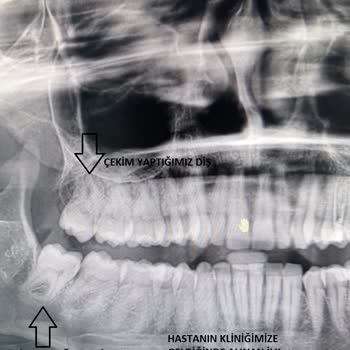

Ben 24.10.2024 Sakadent'te 20'lik dişimi çektirdim eksik tedavi uygulamasından ötürü tekrar başka bir özele gitmek zorunda kaldım. Çünkü 20lik dişin apse yapmış olmasına rağmen dikiş atılmadı İlk tedavide dikiş atılması gerekirken bir şey yapılmadığını şikayet etmek istiyorum. Hatta ve hatta çekilen...